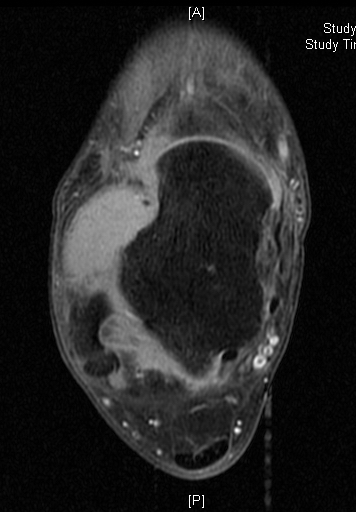

MRI

Shows multiloculated, heterogeneous mass.

“Triple Signal Intensity sign”; hypointense, isointense and hyperintense with fat on T2 – weighted MRI imaging. This sign is present in 30 to 50% of the cases. (Fig.3)

Under contrast enhancement Synovial Sarcoma appears heterogeneous and demonstrate areas of nodular enhancement.

In approximately 30% of cases a multiple vascular cannel may be identified

Synovial sarcomas may have a cystic appearance and are often mistaken for ganglion cysts especially those adjacent to tendons and in the foot and ankle.